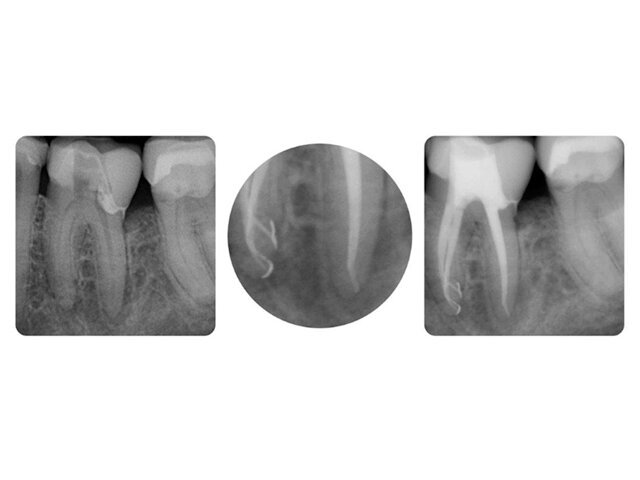

Na rozdíl od ošetření zubního kazu, během kterého choroboplodné zárodky odstraníme čistě mechanickou exkavací a progresi nemoci tak zastavíme, u infikované nekrózy pulpy nedochází ke změknutí dentinu. Redukce mikroorganizmů dosáhneme především efektivním výplachem. Kořenový kanálek je často tenký jako lidský vlas, proto jej potřebujeme rozšířit natolik, abychom nechali působit výplachový roztok v celé jeho délce. Rozšiřuji tedy kořenový kanálek a postupně vyplachuji dvěma roztoky: EDTA a NaOCl.

Ošetřující si jednoduše musí být jistý, že koncentrace souhlasí. Pokud by koncentrace NaOCl přesáhnutím exspirace nebo špatnou přípravou klesla pod 1 %, mělo by to na výsledky mého ošetření fatální dopad. Biofilm by nebyl kompletně zasažen účinkem výplachu nebo by v isthmech či ramifikacích zůstaly vitální tkáně. Průmyslově vyráběné přípravky, zvláště když jsou schválenými lékařskými přípravky (jako např. HISTOLITH®), podléhají pravidelné kontrole a mají úřední záruku kvality. Tak nemám slabé místo v tomto článku mého endodontického řetězce. Kromě toho je každá láhev vybavena pevně zabudovaným odběrovým systémem ESD, který zajišťuje větší komfort a bezpečnost při používání. Roztok NaOCl lze stejně jako EDTA natáhnout z láhve přímo do stříkačky. Navíc je na láhvi uvedena doba trvanlivosti, což garantuje, do kdy zůstává koncentrace zachována. Díky odběrovému systému (Luer--Lock) lze láhev napojit přímo na automatické výplachové jednotky jako např. Endopilot nebo SAF EndoStation.

U NaOCl kladu důraz na tuto vyšší koncentraci, protože účinek rozpouštění tkání (vztaženo na organické složky) je lepší. Při používání 5% koncentrace je důležité zajistit dobrou izolaci pomocí koff erdamu a předejít přetlačení výplachového roztoku přes apex. Účinek NaOCl na rozpouštění měkkých tkání je pro odstranění zbytků tkání a biofilmu právě tak důležitý, jako je účinek EDTA na anorganickou složku. Preparační drť ucpává postranní kanálky a oslabuje tak účinek NaOCl. Z tohoto důvodu je třeba kořenový kanálek po opracování vypláchnout EDTA a po jedné minutě působení následně opět použít NaOCl. NaOCl pak může lépe proniknout do všech míst v kanálku.